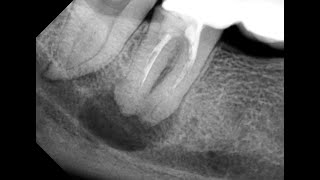

Профессиональную гигиену полости рта при пародонтозе проводят с использованием специальных инструментов, таких как ультразвуковые и механические скейлеры. Они помогают эффективно удалить налет с зубов и областей под десневыми краями, где обычная чистка зубной щеткой затруднена.

Пародонтоз характеризуется воспалением пародонта - тканей, окружающих зубы. При этом зубной налет и зубные отложения могут стимулировать рост бактерий и усиливать воспаление. Поэтому регулярная профессиональная гигиена играет важную роль в лечении пародонтоза.

Лечение пародонтоз — Кюретаж и скалер ©